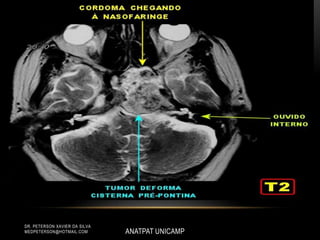

CORDOMA DE CLIVUS

• Sinal iso ou hipointenso em Tl.

• Hipersinal em T2.

• Captação heterogênea de contraste, com

aspecto de favo de mel

(áreas de hipossinal em Tl).

• Sinal isoou hipointenso em Tl. • Hipersinal em T2. • Captação heterogênea de contraste, com aspecto de favo de mel (áreas de hipossinal em Tl). ANATPAT UNICAMP DR. PETERSON XAVIER DA SILVA MEDPETERSON@HOTMAIL.COM CORDOMA DE CLIVUS

• #9 • Sinal iso ou hipointenso em Tl. • Hipersinal em T2. • Captação heterogênea de contraste, com aspecto de favo de mel (áreas de hipossinal em Tl).

• #11 • Sinal iso ou hipointenso em Tl. • Hipersinal em T2. • Captação heterogênea de contraste, com aspecto de favo de mel (áreas de hipossinal em Tl).

• #13 Caracterizam-se por massa lobulada de consistência amolecida, coloração acinzentada, localmente agressivos, com intensa infiltração óssea (lesão lítica). Por esse aspecto, a neoplasia acomete predominantemente o espaço extradural, podendo, no entanto, apresentar, em alguns pacientes, envolvimento intradural. • Sinal iso ou hipointenso em Tl. • Hipersinal em T2. • Captação heterogênea de contraste, com aspecto de favo de mel (áreas de hipossinal em Tl).